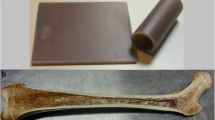

Yellow bone marrow temperature calibration

Bovine yellow bone marrow was extracted from the medullary cavity of a femur segment, filled into a petri dish, and placed in an insulated cylindrical container. The container was filled with deionized water, which was circulated by a peristaltic pump (Masterflex, Cole Parmer, Vernon Hills, IL) through a heat exchanger. The heat exchanger was placed in a temperature-regulated water bath (Polystat R6L, Cole-Parmer) set to the desired temperature. To reduce heat loss from the heat exchanger in the water bath outside the scanner room to the sample container in the scanner bore, all tubes were covered with pipe insulation. The temperature in the water-filled container was monitored with a fiber optic sensor (Luxtron, LumaSense Technologies, Santa Clara, CA). The time necessary for temperature equilibration within the sample has been determined previously [23] by measuring the time it took to reach equilibrium after a 10 °C change in circulating water temperature which was found to be approximately 20 min.

Intact cortical bone ablation

In order to test T2-based temperature monitoring in conditions more closely resembling those of a bone treatment, we performed ablation in an intact ex vivo porcine femur (sonication time: 20 s, acoustic power: 30 W) using the in-table transducer of the ExAblate system, operating at 1.15 MHz. The focus of the sonication was placed within the yellow marrow of the diaphysis of the femur with the ultrasound beam path intersecting the cortical bone. Bone marrow T2 was quantified with a double-echo FSE sequence with water suppression (TE = 35/186 ms, TR = 1500 ms, echo train length = 40, FOV = 32 cm, 128 × 128 matrix size, 10-mm slice thickness, 15 s/slice).